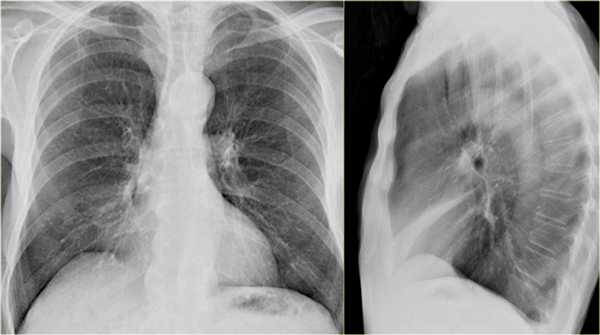

- Симптом силуэта — нечеткие границы правых отделов сердца.

- Трехгранные изменения высокой плотности, визуализирующиеся на боковой рентгенограмме, являются результатом ателектаза средней доли правого легкого.

При ателектазе средней доли правого легкого подъем диафрагмы навсегда значительно выражен.